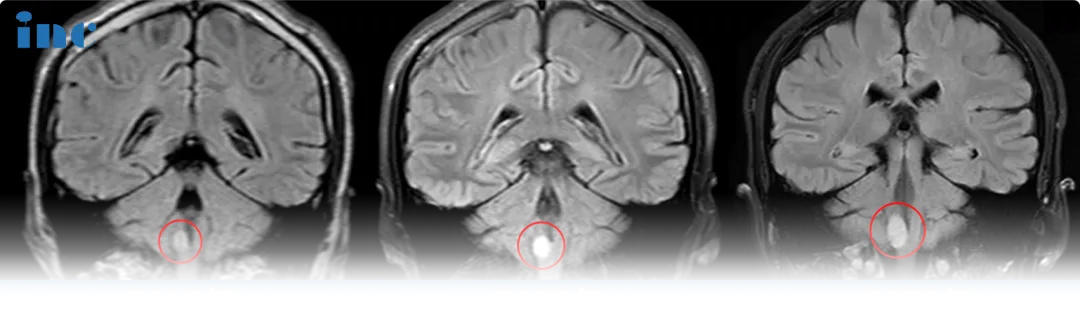

腦干延髓膠質(zhì)瘤影像圖片

腦干延髓膠質(zhì)瘤真實案例影像圖片